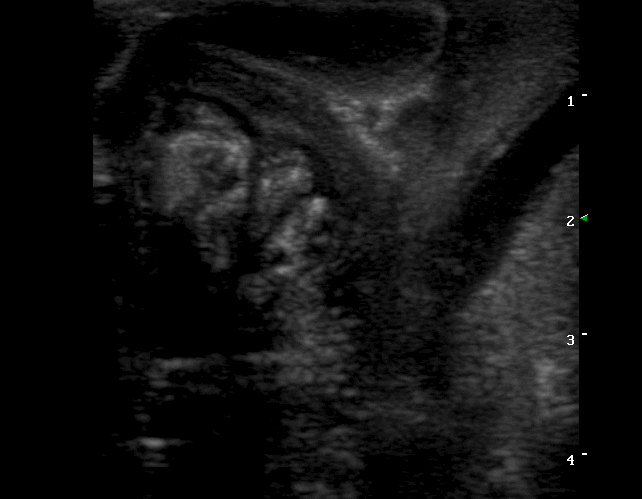

Findings: Distention of large part of the small intestine, caused by intussusception. The blood flow in the mesenteric arteries which supplied the intussusception was normal. The mesenteric lymphnodes were enlarged. A small amount of ascistic fluid was noted.

Ευρήματα: Στον υπερηχοτομογραφικό έλεγχο της κοιλίας βρέθηκε παρουσία εγκολεασμού σε τμήμα του λεπτού εντέρου. Η αιμάτωση των μεσεντέριων αγγείων του εγκολεσθέντος τμήματος εκτιμήθηκε φυσιολογική. Οι μεσεντέριοι λεμφαδένες βρέθηκαν διογκωμένοι με αντιδραστική ηχομορφολογία. Υπήρχε μικρή ποσότητα ασκιτικού υγρού. Οι υπόλοιπες εντερικές έλικες που αφορούσαν το τμήμα του λεπτού εντέρου πριν τον εγκολεασμό βρέθηκαν διατεταμένες .